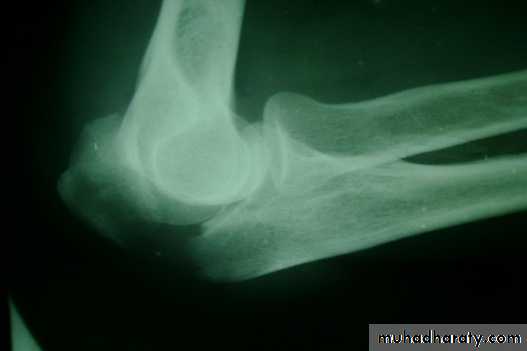

Two views – A fracture or a dislocation may not beseen on a single x-ray film, and at least two views (anteroposterior and lateral) must be taken.

Two joints – In the forearm or leg, one bone may befractured and angulated. Angulation, however, is impossible unless the other bone is also broken, or a joint dislocated. The joints above and below the fracture must both be included on the x-ray films.